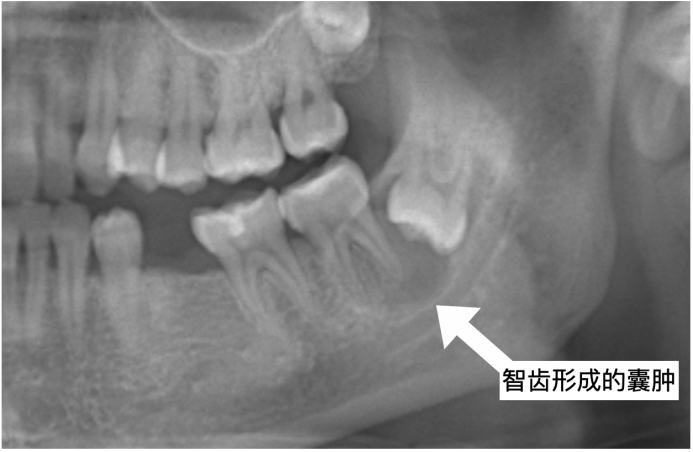

5.阻生齿:这一种类型的牙齿,通常埋在牙槽骨的里面,有可能会伴有囊肿之类的病变。如果有疼痛或者病变,是需要拔除的。 当然这类智齿拔除后,根据创伤大小会产生术后疼痛、面部肿胀、张口受限等一些反应,建议在医生的指导下进行术后用药和护理。